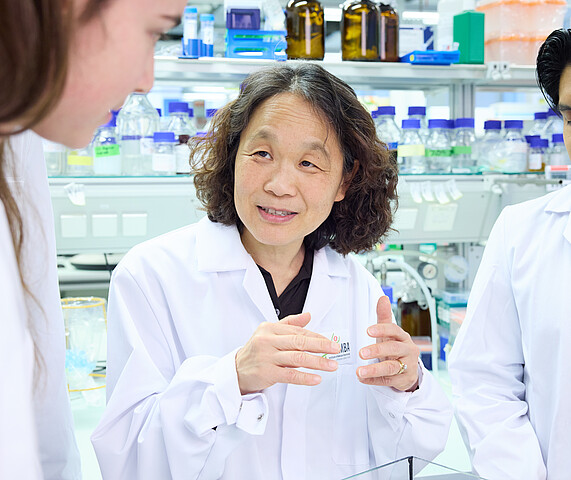

Optimismus angebracht – Life Sciences auf Weltniveau

Elly Tanaka vom IMBA: Europa forscht auf Weltniveau – und Österreich mit Wien an der Spitze sorgt für die besten Bedingungen.